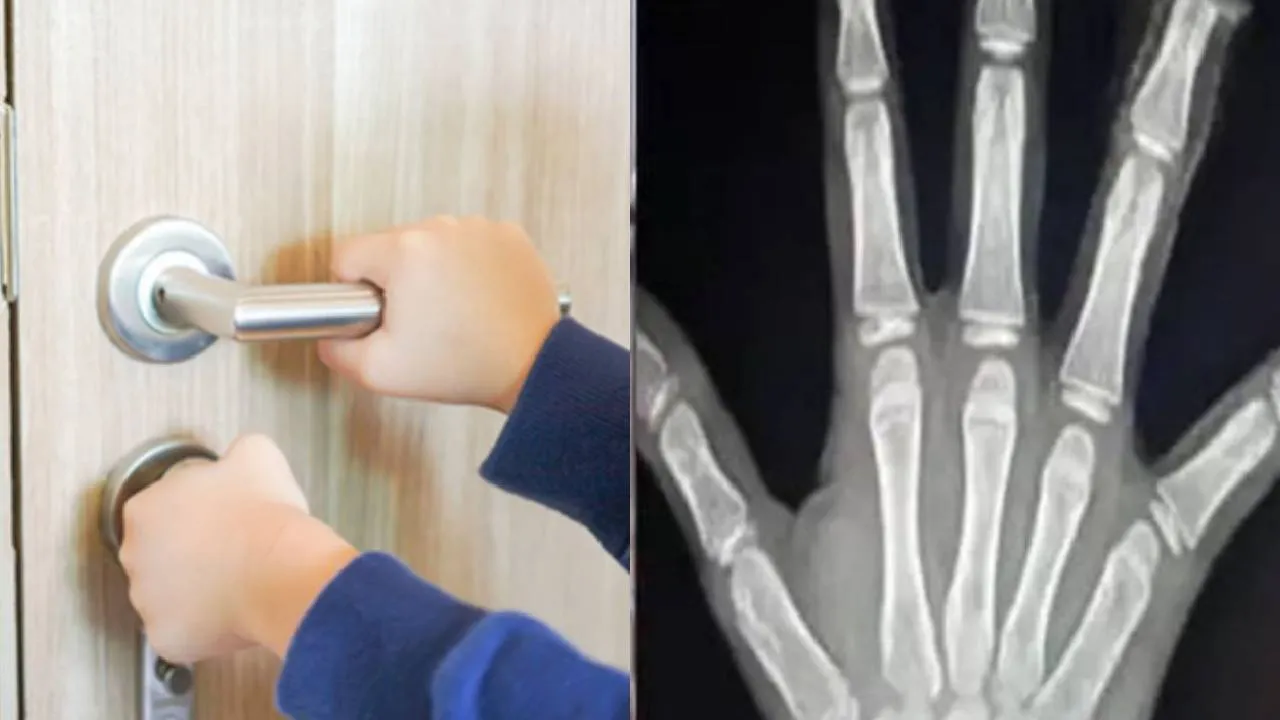

Tumkur News: ಶಾಲೆಯ ಬಾಗಿಲಿಗೆ ಸಿಲುಕಿ ತುಂಡಾದ ವಿದ್ಯಾರ್ಥಿನಿಯ ಕೈ ಬೆರಳು

Tumkur News: ಮಧ್ಯಾಹ್ನದ ಬಿಸಿಯೂಟಕ್ಕೆ ಸರದಿ ಸಾಲಿನಲ್ಲಿ ನಿಂತಿದ್ದಾಗ ಶಾಲೆಯ ಬಾಗಿಲಿಗೆ ಸಿಲುಕಿ 1ನೇ ತರಗತಿಯ ಬಾಲಕಿಯ ಎರಡು ಕೈ ಬೆರಳುಗಳು ತುಂಡಾಗಿರುವ ಘಟನೆಯು ತುಮಕೂರು ತಾಲೂಕಿನ ಗೂಳೂರು ಸರ್ಕಾರಿ ಶಾಲೆಯಲ್ಲಿ ಜರುಗಿದೆ. ಈ ಕುರಿತ ವಿವರ ಇಲ್ಲಿದೆ.

ತುಮಕೂರು, ಫೆ.13: ತಾಲೂಕಿನ ಗೂಳೂರು ಸರ್ಕಾರಿ ಶಾಲೆಯಲ್ಲಿ ಮಧ್ಯಾಹ್ನದ ಬಿಸಿಯೂಟಕ್ಕೆ ಸರದಿ ಸಾಲಿನಲ್ಲಿ ನಿಂತಿದ್ದಾಗ ಶಾಲೆಯ ಬಾಗಿಲಿಗೆ ಸಿಲುಕಿ 1ನೇ ತರಗತಿಯ ಬಾಲಕಿಯ ಎರಡು ಕೈ ಬೆರಳುಗಳು ತುಂಡಾಗಿರುವ ಘಟನೆ (Tumkur News) ನಡೆದಿದೆ.

ಚಿನ್ಮಯಿದೇವಿ ಬೆರಳು ಕಳೆದುಕೊಂಡ ವಿದ್ಯಾರ್ಥಿನಿ. ಶಾಲೆಯಲ್ಲಿ ಮಧ್ಯಾಹ್ನದ ಬಿಸಿಯೂಟ ನೀಡುವ ವೇಳೆ ಚಿನ್ಮಯಿದೇವಿ ಎಂಬ ಪುಟ್ಟ ಬಾಲಕಿ ಇತರ ವಿದ್ಯಾರ್ಥಿಗಳಂತೆ ಊಟಕ್ಕಾಗಿ ಸರತಿಯ ಸಾಲಿನಲ್ಲಿ ನಿಂತಿದ್ದ ಸಂದರ್ಭದಲ್ಲಿ ಬಾಲಕಿ ಆಕಸ್ಮಿಕವಾಗಿ ಶಾಲೆಯ ಬಾಗಿಲಿಗೆ ಕೈ ಇಟ್ಟುಕೊಂಡು ನಿಂತಿದ್ದಳು ಎನ್ನಲಾಗಿದೆ. ಅದೇ ಸಮಯದಲ್ಲಿ 3ನೇ ತರಗತಿಯ ವಿದ್ಯಾರ್ಥಿ, ಅಕಸ್ಮಾತ್ ಆಗಿ ಬಾಗಿಲನ್ನು ಜೋರಾಗಿ ತಳ್ಳಿದ ಪರಿಣಾಮ, ಬಾಗಿಲಿನ ಸಂದಿಯಲ್ಲಿ ಸಿಲುಕಿ ಬಾಲಕಿಯ ಎರಡು ಬೆರಳುಗಳು ತುಂಡಾಗಿವೆ ಎನ್ನಲಾಗಿದೆ.

ಘಟನೆ ನಡೆದ ತಕ್ಷಣ ಗಾಬರಿಗೊಂಡ ಶಾಲಾ ಸಿಬ್ಬಂದಿ, ಸರಿಯಾದ ಪ್ರಥಮ ಚಿಕಿತ್ಸೆ ಅಥವಾ ತುರ್ತು ಆಸ್ಪತ್ರೆಗೆ ದಾಖಲಿಸುವ ಬದಲು, ಪೋಷಕರಿಗೆ ಕರೆ ಮಾಡಿ ಮಗುವನ್ನು ಮನೆಗೆ ಕಳುಹಿಸಿಕೊಟ್ಟಿದ್ದಾರೆ ಎಂಬ ಆರೋಪ ಕೇಳಿಬಂದಿದೆ.

ಶಾಲೆಗೆ ಕಳುಹಿಸಿದ ಮಗು ಸುರಕ್ಷಿತವಾಗಿ ಇರಬೇಕಿತ್ತು, ಆದರೆ ಶಾಲೆಯ ಅಸಡ್ಡೆಯಿಂದಾಗಿ ನಮ್ಮ ಮಗು ಬೆರಳು ಕಳೆದುಕೊಂಡಿದೆ ಎಂದು ಪೋಷಕರು ಅಳಲು ತೋಡಿಕೊಂಡಿದ್ದಾರೆ. ಅಲ್ಲದೇ ತುಂಡಾಗಿ ಬಿದ್ದಿದ್ದ ಬೆರಳನ್ನು ಶಾಲೆಯ ಸಿಬ್ಬಂದಿ ಗುಡಿಸಿ ಬಿಸಾಡಿದ್ದಾರೆ ಎಂದು ಆರೋಪಿಸಿಲಾಗಿದೆ. ಬೆರಳುಗಳು ಇದ್ದಿದ್ದರೆ ಜೋಡಿಸಬಹುದಿತ್ತು ಎಂದು ವೈದ್ಯರು ಹೇಳಿದ್ದಾರೆ.

ಬಾಲಕಿಯ ಕೈ ಬೆರಳುಗಳು ತುಂಡಾಗಲು ಶಾಲೆಯ ಬಾಗಿಲನ್ನು ಮತ್ತೊಬ್ಬ ವಿದ್ಯಾರ್ಥಿ ಜೋರಾಗಿ ತಳ್ಳಿದ್ದೇ ಕಾರಣ ಎಂಬ ಆರೋಪ ಕೇಳಿಬಂದಿದೆ. ಆದರೆ, ಬಿಸಿಯೂಟದ ಸಮಯದಲ್ಲಿ ಶಿಕ್ಷಕರು ಅಥವಾ ಅಡುಗೆ ಸಿಬ್ಬಂದಿ ಸರಿಯಾದ ಉಸ್ತುವಾರಿ ವಹಿಸಿದ್ದರೆ ಈ ಅನಾಹುತವನ್ನು ತಪ್ಪಿಸಬಹುದಿತ್ತು ಎಂದು ಪೋಷಕರು ಕಿಡಿಕಾರಿದ್ದಾರೆ.